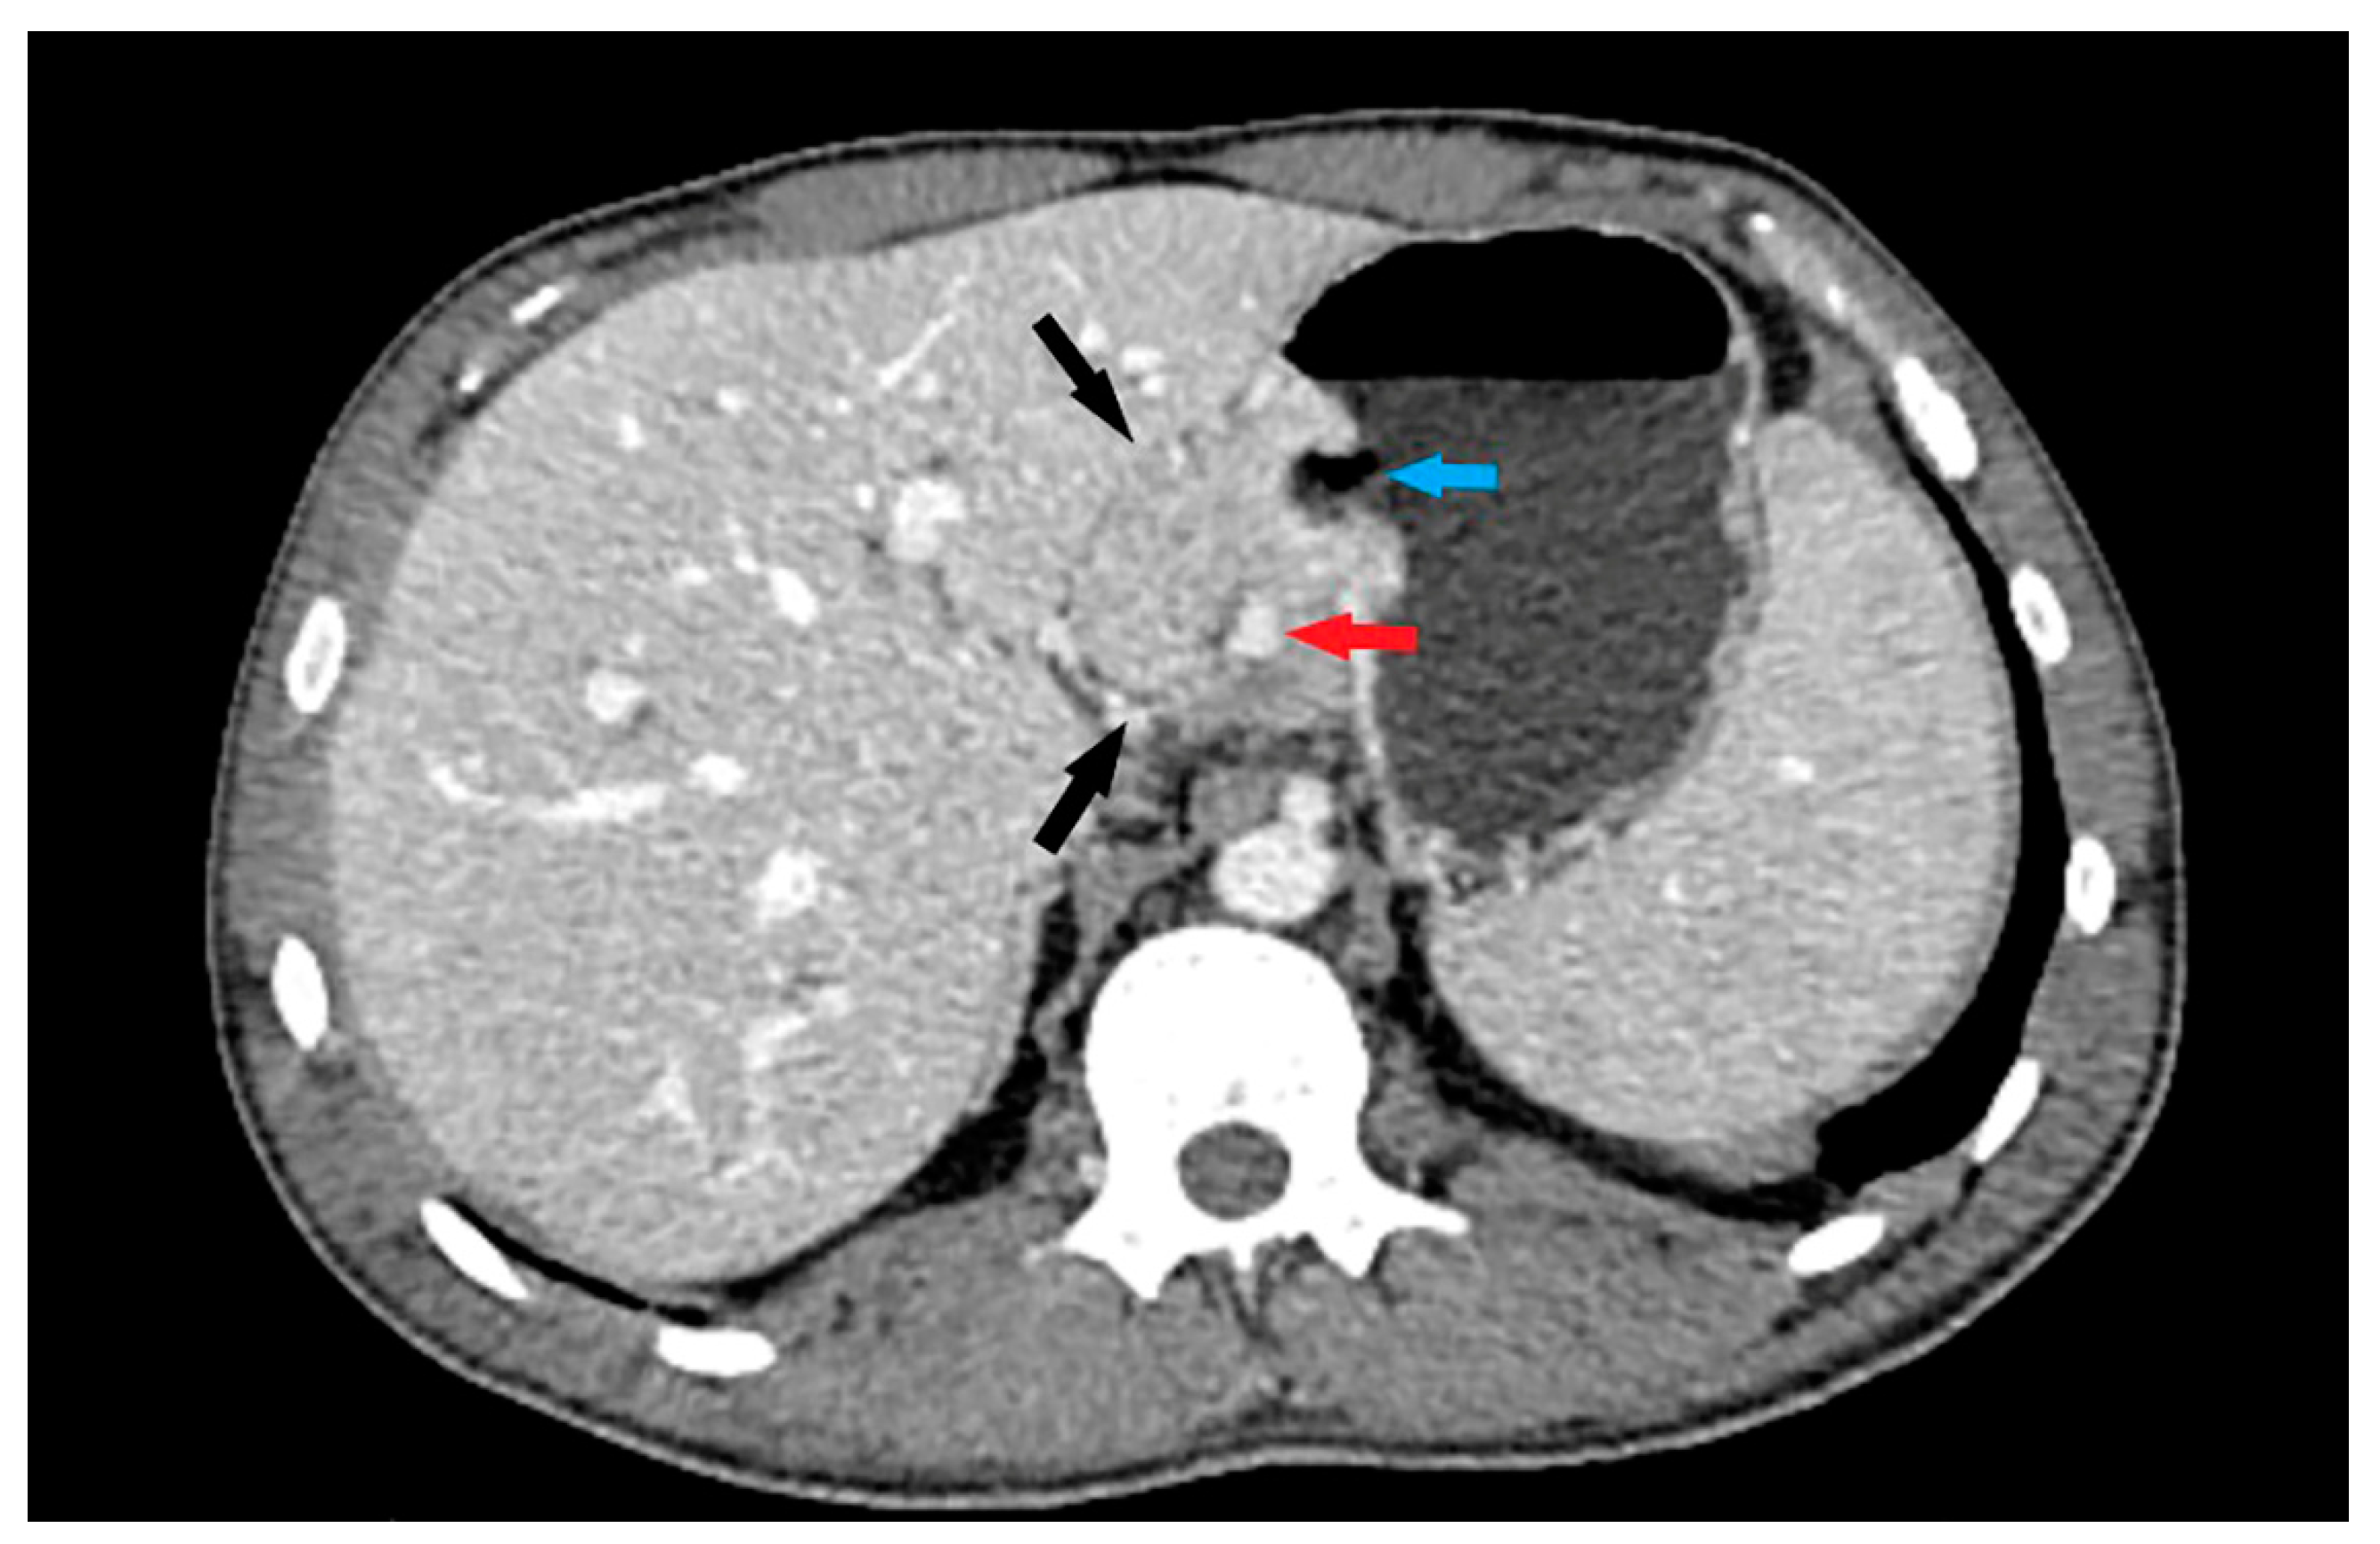

- Maximum diameter: the largest diameter of the tumor in mm (Figure 1);

- Tumor shape: regular or irregular (Figure 1);

- Growth mode: exophytic/mixed and endophytic (Figure 1);

- The presence of visible enlarged vascular structures draining/feeding the tumor (EFDV “enlarged feeding or draining vessel”) (Figure 6);